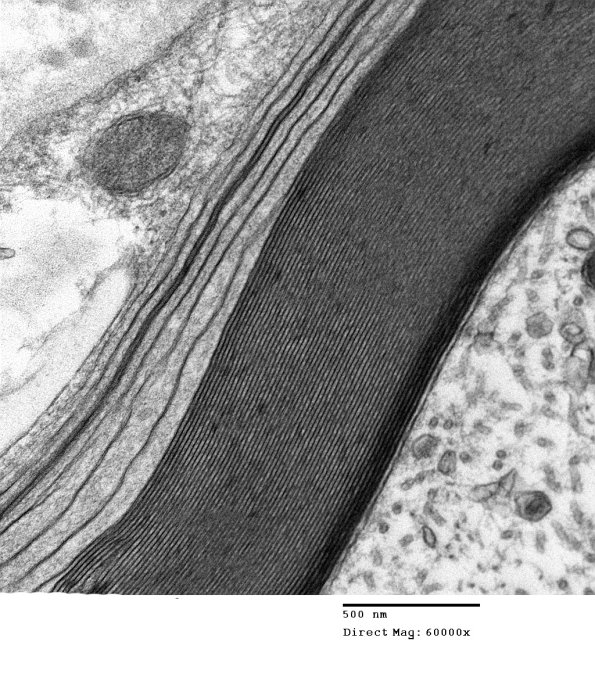

6B2B Anti-MAG NP (Case 6) EM 026A - Copy

An unusually shaped axon with WSM seen at several magnifications. (electron micrographs)